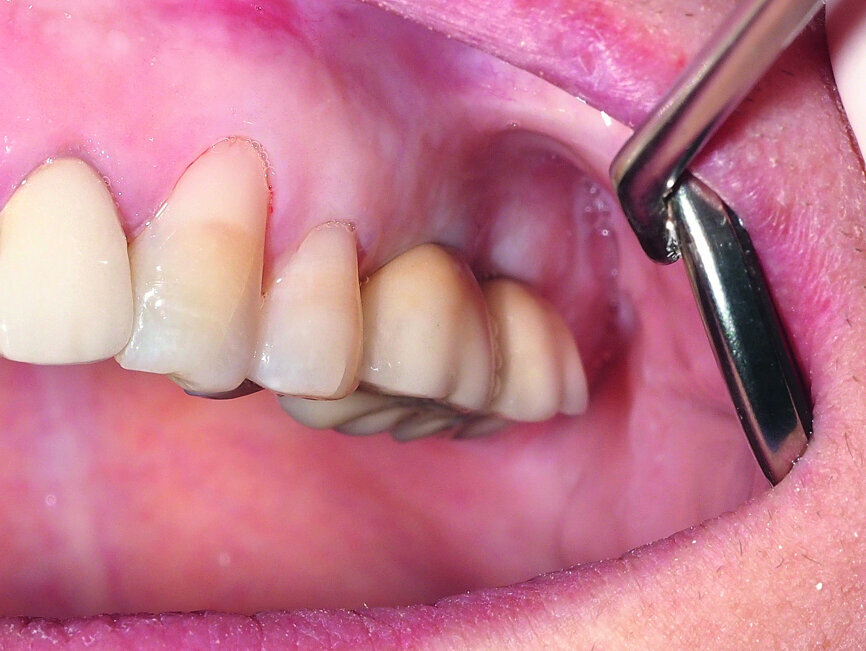

Fig. 15: Combination of full- and partial-thickness flap elevation.

A demonstration of this technique is shown in Figures 13 to 20. This case presents an elderly woman who had lost her teeth in the lateral mandible decades ago. Being a healthy non-smoker with good oral hygiene, no history of periodontal disease and low masticatory forces, she was an adequate candidate for bone grafting together with implant placement. The future restorative margins allowed the usage of ridge splitting (Figs. 13 & 14). Therefore, we opted for a ridge split with vertical releases carried out utilising a partial-thickness flap. The periosteum was left attached in order not to impede the perfusion of the buccal plate (Fig. 15). After ridge splitting, the buccal and lingual plates were separated with the use of bone spreaders (Split-Control Plus, Meisinger) to allow the placement of two GC Aadva Standard implants, one of 3.3 mm in diameter and 8.0 mm in length and the other measuring 4.0 mm in diameter and 8.0 mm in length (Figs. 16–18).